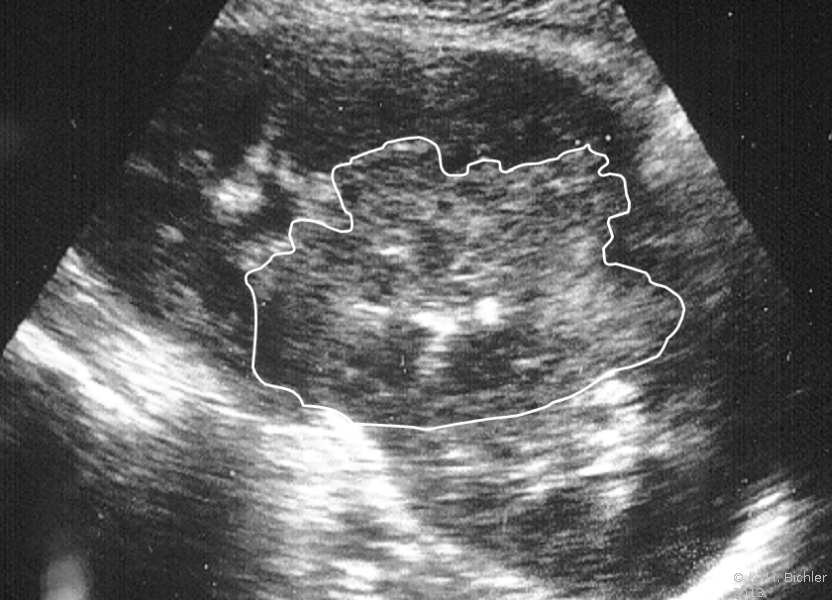

Beispielhaft die Darstellung eines ausgedehnten Nierenabszesses in Sonographie, CT und AUR (Abbildung 6).

Die Abbildung zeigt als weiteres Beispiel die sonographische Darstellung eines ausgedehnten paranephritischen Abszesses (Abbildung 7).